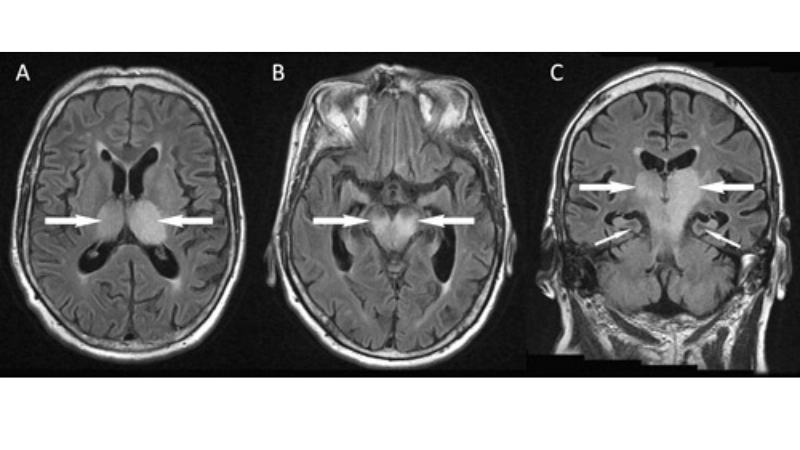

Image description of Murray Valley Encephalitis

Murray Valley Encephalitis is a rare but serious viral infection transmitted by mosquitoes, primarily affecting the brain and nervous system, with potential life-threatening complications.